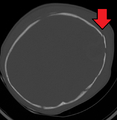

|

Subdural hematoma (arrow), bleeding between the dura mater of the meninges and the brain, commonly occurs in abusive head trauma | |